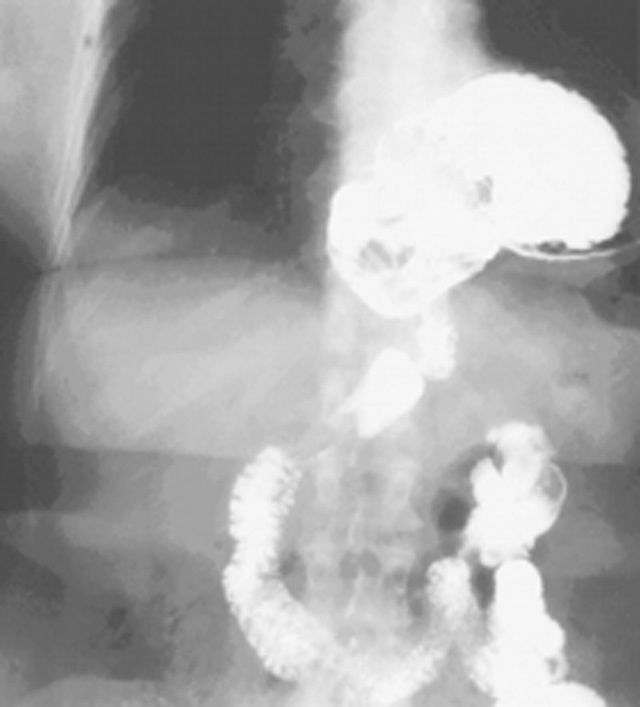

What sign would you expect in this patient?

Bowel sounds in lung fields

(Rolling hernia/paraesophageal hernia)

Describe the pathogenesis of this type of hernia.

Widening of the diaphragmatic hiatus and relaxation of the phreno-esophageal ligament